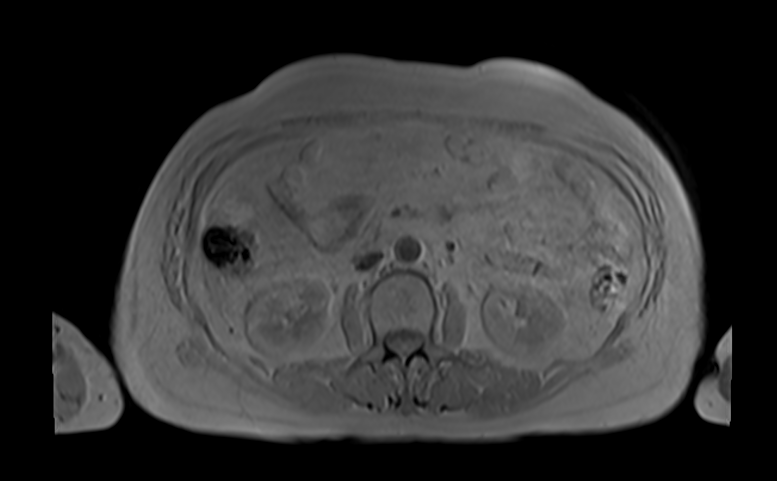

3. 磁共振成像(MRI)

工作原理 : MRI利用强磁场和射频波,使人体内的氢原子核(主要存在于水和脂肪中)产生共振信号。不同组织中的氢原子信号差异通过接收线圈捕捉并转化为图像。

成像技术 :

- T1加权成像(T1-weighted Imaging) :提供高分辨率的解剖细节图像,脂肪显亮,水显暗。适用于显示解剖结构。

- T2加权成像(T2-weighted Imaging) :对病变敏感,水显亮,能突出水肿和炎症。适用于检测病变区域。

- 扩散加权成像(DWI) :对急性中风和肿瘤有高度敏感性,能够检测组织的微观运动。

应用 :

- 脑、脊柱、肌肉骨骼系统的精细成像 :高分辨率成像,有助于复杂解剖结构的评估。

- 软组织病变(如肿瘤、炎症)的诊断 :能够清晰显示软组织结构,有助于早期诊断。

- 心脏、血管成像 :提供无创的心脏和血管详细成像,有助于评估心脏功能和血管病变。